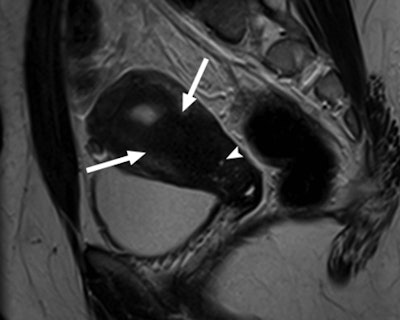

A total of 115 rudimentary uteri were found in the 66 patients, with one or two rudimentary uteri in 61 women (92%). Of those 61 subjects, 54 (82%) had bilateral rudimentary uteri and seven (11%) had unilateral rudimentary uteri. Five individuals (8%) had no uterine remnants.

Mean uterine volume was 6.4 mL (range, 0.4 mL to 80.2 mL), with 18 uteri having a volume greater than 10 mL.

MRI also detected two uteri containing intraluminal blood, and two uteri showed signs of adenomyosis, indicating functioning endometrial tissue. The same two patients with an indication of adenomyosis were experiencing pain.

"Two important findings in our study are the large size (larger than 80 mL) and variable appearances of some of the rudimentary uteri," Hall-Craggs and colleagues noted. "Although large, these uteri did not have a conventional structure; there was no cervix, and the uterine shape was not organized into a fundus and body with ostia. Although some differentiation into layers was seen, this generally occupied a small central proportion of the uterus."